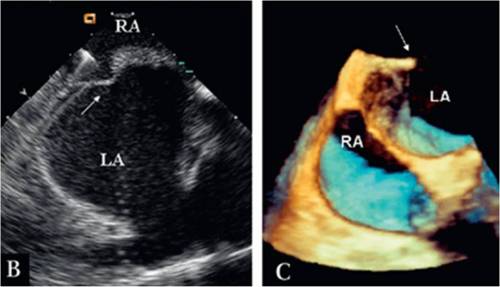

Newer modalities for ASD imaging

Intra cardiac echo and real time 3D TEE will facilitate the ASD device procedures

Image source : Heart 2010;96:1409e1417